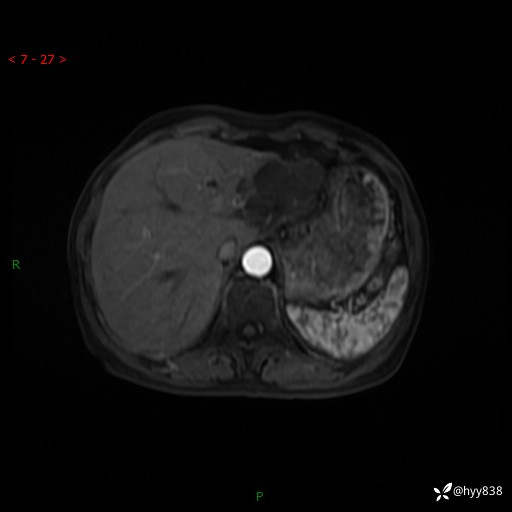

辅助检查:MRI

肝脏MRI平扫(同反相位)

T2WIfs+DWI

增强(动脉期+静脉期+延迟期)